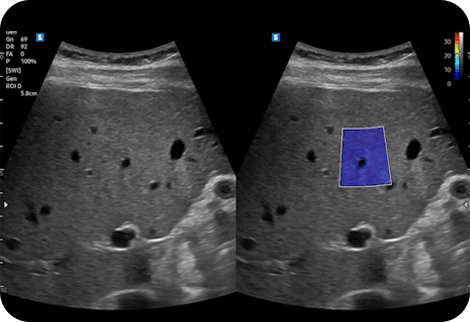

Quantitative measurement of liver fat

with ultrasound signal

TAI™ (Tissue Attenuation Imaging) provides quantitative tissue attenuation measurement to assess steatotic liver changes.

TSI™ (Tissue Scatter distribution Imaging) provides quantitative tissue scatter distribution measurement to assess steatotic liver changes.

Hepato-renal index with

automated ROI recommendation

HRI (Hepato Renal Index) is an index to quantify steatosis of a liver by comparing echogenicity between liver parenchyma and renal cortex. EzHRI™ places 2 ROIs on the liver parenchyma and renal cortex and provides HRI ratio.